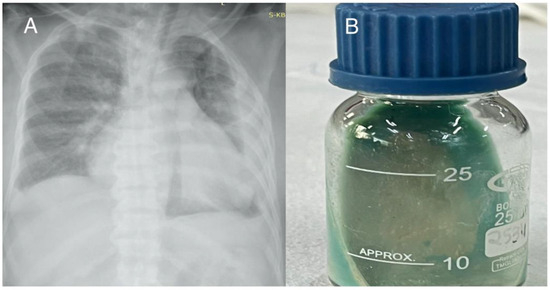

Introduction: Infective endocarditis (IE) is a disease that may frequently lead to significant morbidity and is associated with high mortality rates. Even though IE is classically caused by Gram-positive bacteria, Gram-negative bacteria may seldom ca...